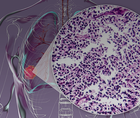

Evaluating Dato-DXd for EGFR-Mutated Advanced NSCLC: Data from a Pooled Analysis

Understanding Extensive-Stage Small Cell Lung Cancer: Advancements and Ongoing Challenges